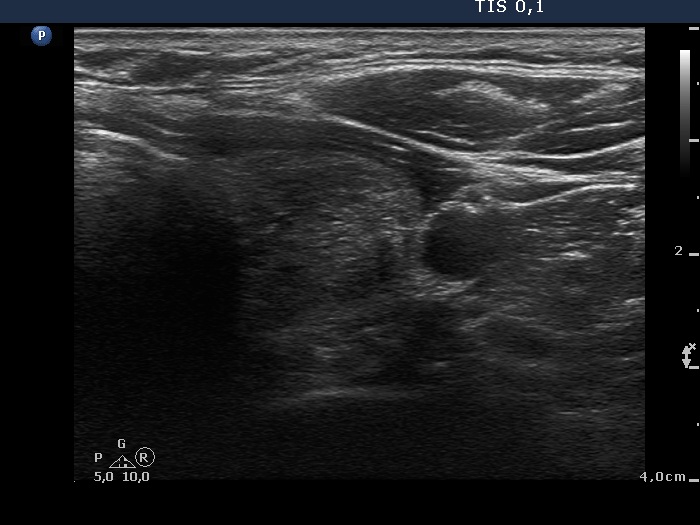

Parathyroid lesions - case 907 (ultrasonographic picture 11)

Lower part of the left lobe, transverse scan. There is a hyperechogenic, inhomogeneous nodule.